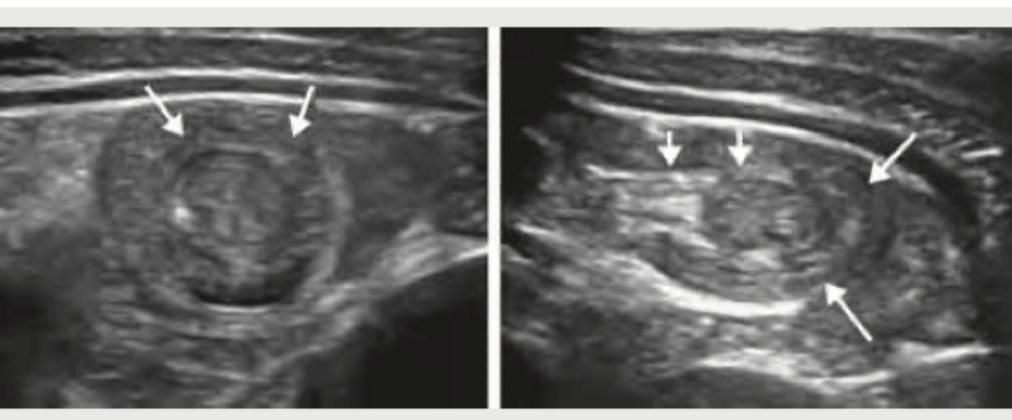

Neonate is brought at 3 weeks of age, with projectile vomiting. USG was performed and is shown below. When can the abdominal mass in this condition be best palpated?

USG abdomen of a 9-month-old child as shown below denotes:

Explanation: ***During feeding*** - In **hypertrophic pyloric stenosis**, the characteristic **"olive" mass** formed by the thickened pylorus is most easily palpable **during feeding or immediately after vomiting**. - During this time, the infant’s abdominal muscles are relaxed, making palpation of the mass in the **epigastrium (right upper quadrant)** more successful. *In umbilical area* - The umbilical area is typically where **omphaloceles** or **umbilical hernias** are found, not the pyloric mass. - The pylorus is located much higher in the epigastric region, to the right of the midline. *In epigastric area* - While the pyloric mass is located in the **epigastric area**, palpation is more difficult when the infant is crying or agitated. - The question asks when it can be *best* palpated, emphasizing the conditions under which it is most detectable. *In Right upper quadrant* - The pylorus is indeed located in the **right upper quadrant/epigastrium**. - However, the optimal timing for palpation is during feeding or after vomiting, as the infant's abdomen is relaxed at that point.

Explanation: ***Intussusception*** - The ultrasound image clearly shows a "target sign" or "doughnut sign" in transverse view, and a "pseudokidney sign" or "sandwich sign" in longitudinal view, which are **pathognomonic for intussusception**. - Intussusception is the telescoping of one part of the intestine into an adjacent part, commonly presenting in infants with **abdominal pain**, **vomiting**, and **currant jelly stools**. *Meckel's diverticulum* - A Meckel's diverticulum is a **remnant of the omphalomesenteric duct** and typically appears as a blind-ended pouch on imaging, not a concentrically layered mass. - While it can cause bleeding or obstruction, it generally does not produce the characteristic sonographic appearance seen here. *Rectal polyp* - A rectal polyp is an **abnormal growth of tissue** protruding from the lining of the rectum. - Ultrasound of a rectal polyp would show a distinct mass in the rectum, which is not depicted in this image of the small or large bowel. *Congenital hypertrophic pyloric stenosis* - This condition involves **thickening of the pyloric muscle**, leading to gastric outlet obstruction, and is characterized by a "cervix sign" or "target sign" in the pylorus on ultrasound. - The image shown depicts a larger, more complex bowel involvement (likely ileocolic), not a focal pyloric thickening.